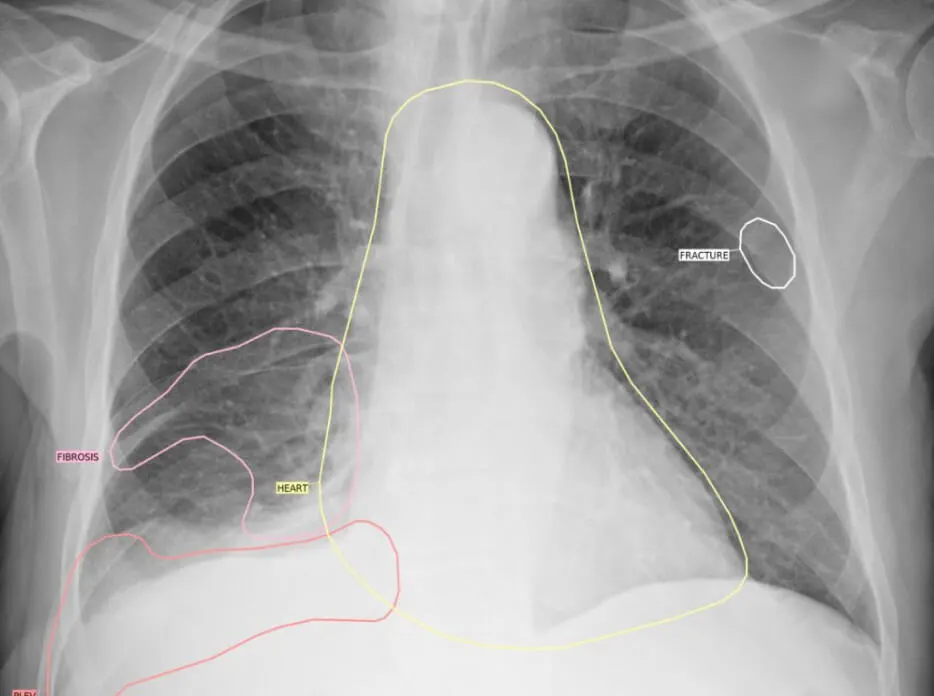

Chest CT

An AI-powered solution efficiently detects pathologies in medical imaging, including cancer, cancer nodules in the early stages. It supports X-rays, CT scans, and MRIs, reducing diagnosis time and enhancing hospital capacity by streamlining workflows.

With a focus on enhancing diagnostic precision and optimizing radiologist workflows, Gamma leverages advanced AI algorithms to analyze X-rays, CT scans, and MRIs efficiently.